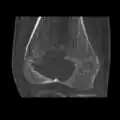

| Chondoblastoma of thigh bone near knee (CT scan, non-contrast) | |

1. a. X-ray of chondroblastoma of thigh bone near knee -

1. b. CT scan shows chondroblastoma of thigh bone near knee more clearly -

1. c. CT scan of chondroblastoma of thigh bone near knee (cross-section view) -